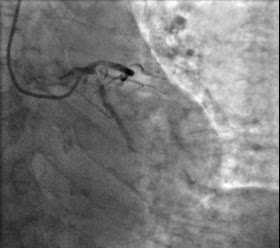

В рентгеноперационной у нее было обнаружено тяжелое многососудистое заболевание, и устье огибающей было описано как виновное поражение. В заметке указано, что первая картинка огибающей показала 99% стеноз с потоком TIMI 2, но затем (до вмешательства) была замечена полная окклюзия в реальном времени (100% стеноз , TIMI 0). Вскоре после засвидетельствованной окклюзии у пациентки произошла остановка сердца вследствие фибрилляции желудочков, после чего ее немедленно реанимировали с помощью 1 дефибрилляции. Процедура была описана как очень сложная из-за тяжелой многососудистой ИБС, но в конечном итоге ЧКВ в устье ОА было успешно выполнено. Было отмечено, что другие сосуды могут потребовать более позднего этапного ЧКВ и внутрисосудистой литотрипсии.

До вмешательства.

После вмешательства.